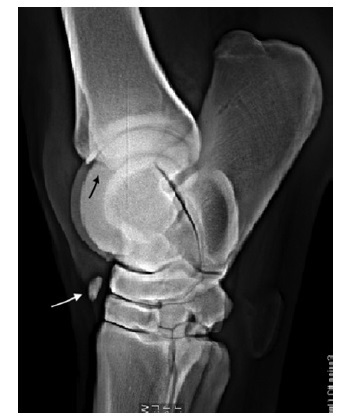

Figure 99-24. (A) DMPLO radiographic view of the tarsus showing a distal intermediate ridge of the tibia OCD lesion. (B) DMPLO radiographic view of the tarsus showing a large lateral trochlear ridge OCD lesion.

Figure 99-28. Lateromedial radiographic view of a tarsal region showing a loose fragment at the distal aspect of the joint cavity (white arrow). It is most likely located in the PIT. The origin of the fragment is the distal intermediate ridge of the tibia (black arrow